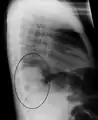

| A chest X-ray showing a very prominent wedge-shape bacterial pneumonia in the right lung | |